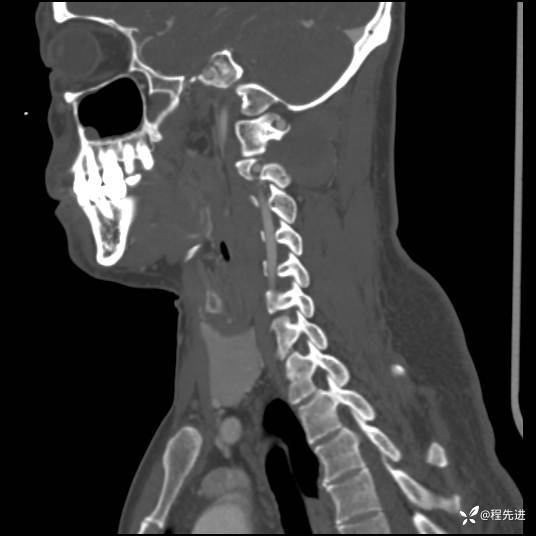

CT平扫+增强:

现病史:患者3个月前低头工作后感颈部疼痛,隐痛,活动颈部后稍好转,无上肢麻木不适,无肢体活动障碍,无头晕头痛,3个月来疼痛反复发作

患者性别:男

患者年龄:43岁

主诉:颈部疼痛3个月